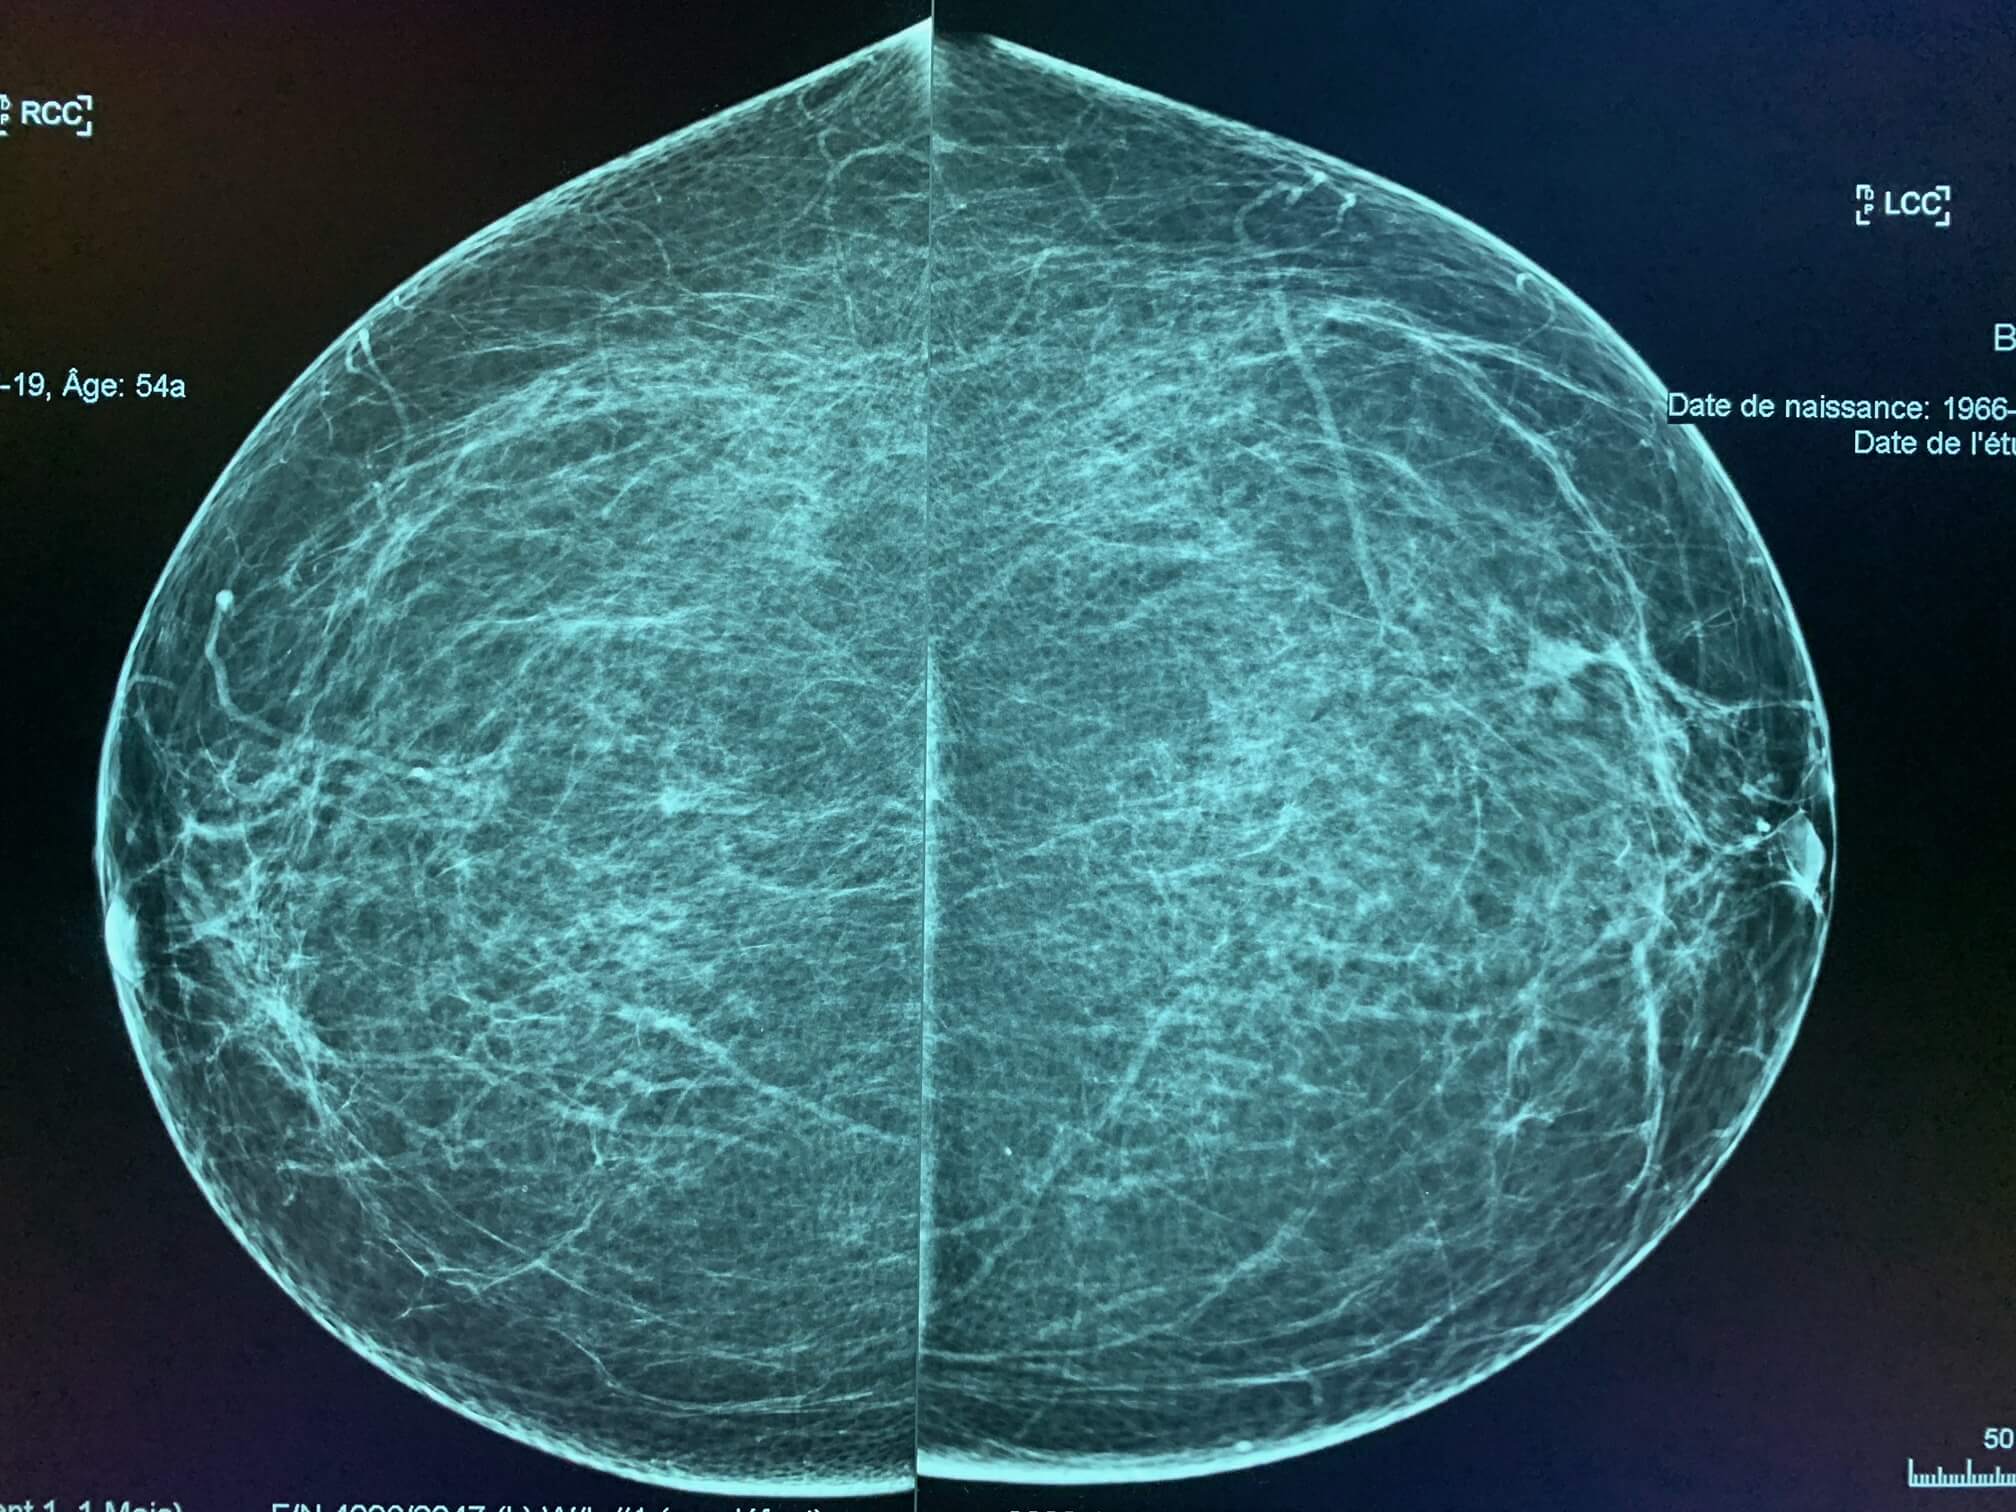

54-year-old woman, routine screening mammography.

MammoScreen™ points to a left external retroareolar opacity.